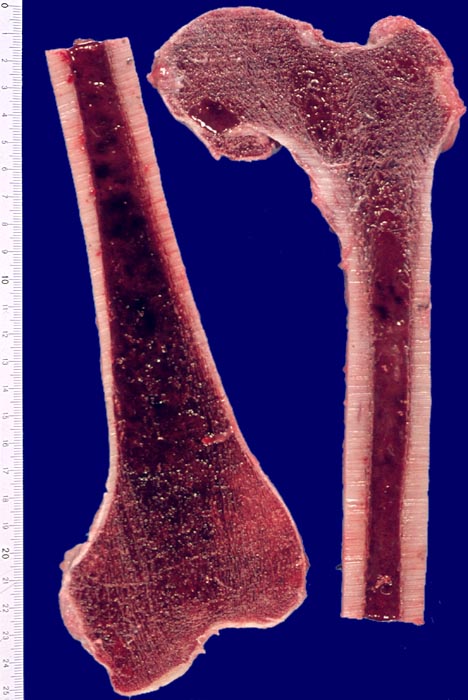

Akute myeloische Leukämie: Hyperplastisches Knochenmark

Knochen, Femur

Das gesamte Mark des Femurknochens (im Normalfall nur das proximale Drittel bis etwa die Hälfte) ist blutbildend und aus diesem Grund dunkelrot gefärbt.

Im Normalfall enthält das proximale Drittel bis etwa die Hälfte des Femurknochens beim Erwachsenen blutbildendes Mark, der Rest besteht aus gelbem Fettmark.